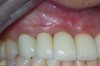

Fig 6. Clinical health of tissue 6 years post-repair (2014).

Figure 6